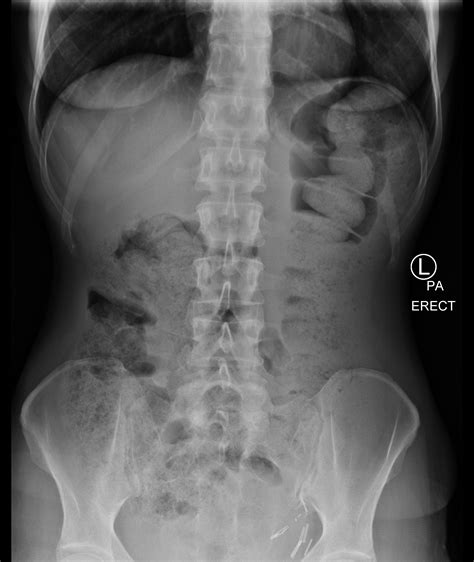

1. The patient is positioned on an X-ray table, usually lying on their back.

4. Multiple images may be taken from different angles to provide a comprehensive view of the abdominal area.

Interpreting the results of a Normal Abdominal X Ray requires expertise in radiology. The images are reviewed by a radiologist who looks for various signs and abnormalities, including:

• Air or gas patterns in the intestines

• Presence of foreign bodies

• Abnormalities in the shape or position of organs

• Signs of obstruction or perforation

If the Normal Abdominal X Ray shows no abnormalities, it is considered normal. However, if any issues are detected, further diagnostic tests or treatments may be recommended.